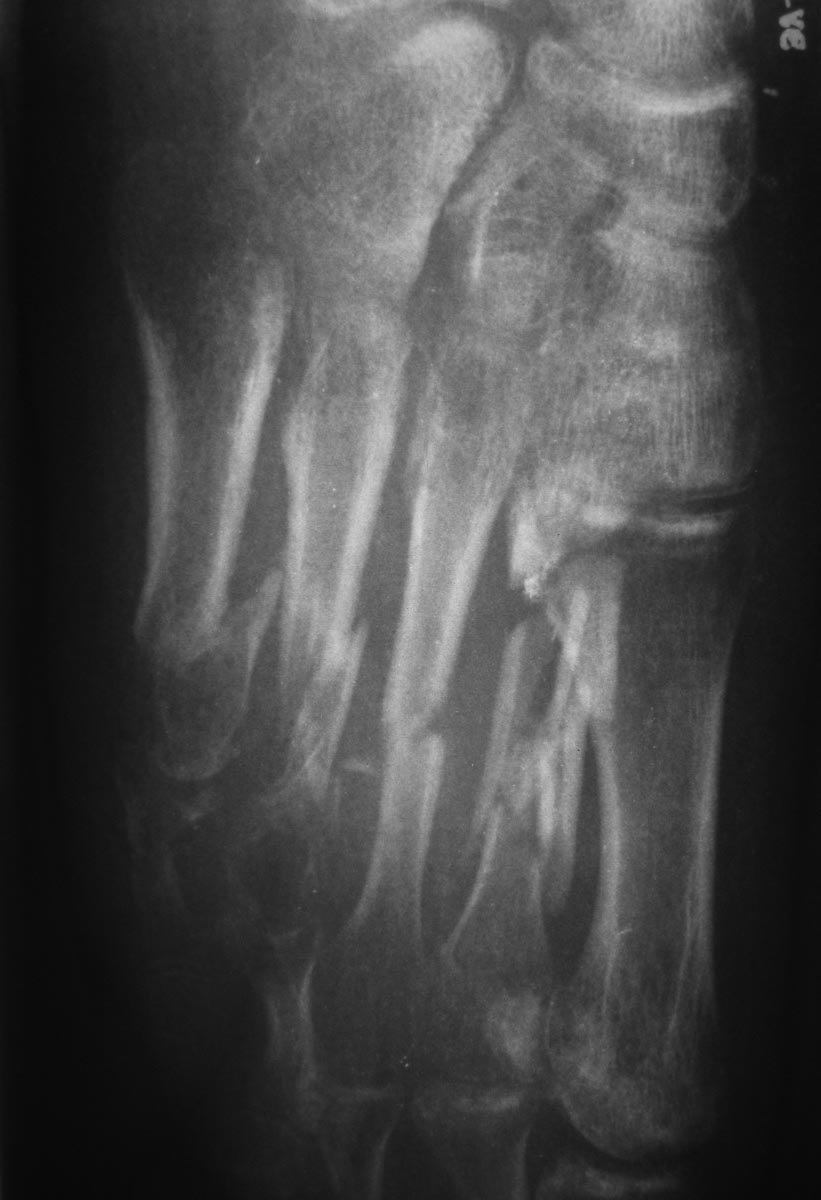

Пациентка 19 лет 11.05.13 получила травму в результате ДТП. диагноз:

Открытые 3а степени оскольчатые переломы диафиза 2-5 плюсневых костей,

перелом проксимальной фаланги 5 пальца, разрыв сухожилия разгибателя 4

пальца правой стопы. При поступлении выполнено ПХО открытых переломов,

фиксация спицами. Рана тыла стопы заживала без воспаления, однако

имелся частичный некроз кожного лоскута. По снятии швов произведена

иммобилизация циркулярной повязкой. Снимки стопы через 2,5 мес.

иммобилизации.

Прошу помочь в определении дальнейшей тактики:

- разрешить частичную нагрузку и продолжить иммобилизацию - на сколько(?)

- продолжить иммобилизацию без нагрузки

- предложить оперативное лечение?